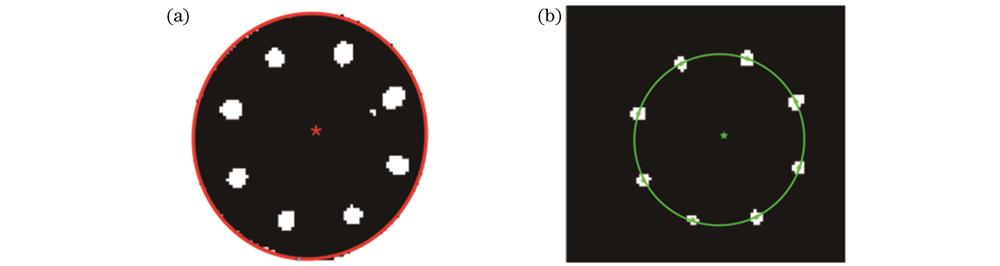

本文采取了一种高精度椭圆识别的方法[18],对T1阈值分割后的图像进行瞳孔边缘检测、椭圆拟合及中心计算。该方法处理的结果如

图 7. 瞳孔中心与光轴中心示意图。(a)瞳孔识别及中心点;(b)光轴椭圆拟合及中心点

Fig. 7. Schematic diagrams of pupil center and optical axis center. (a) Pupil identification and center point; (b) optical axis ellipse fitting and center point

经阈值T2分割后的图像中的8个白色小区域代表8个LED灯珠在角膜上反射的光点,这8个光点的中心即为测量光轴的中心。首先通过连通域标记的方法[19],将这8个小区域进行标记,然后利用质心法计算其质心坐标,最后对8个质心坐标进行最小二次椭圆拟合,并求取椭圆中心,该中心点即为测量光轴在图像上的坐标。本步骤处理后的结果如

在得到瞳孔中心和光轴的图像坐标后,计算两者之间的相互关系,再通过位移台X和Y方向的移动,使得瞳孔中心与光轴重合,实现瞳孔对准。瞳孔中心与光轴相对位置的示意图如